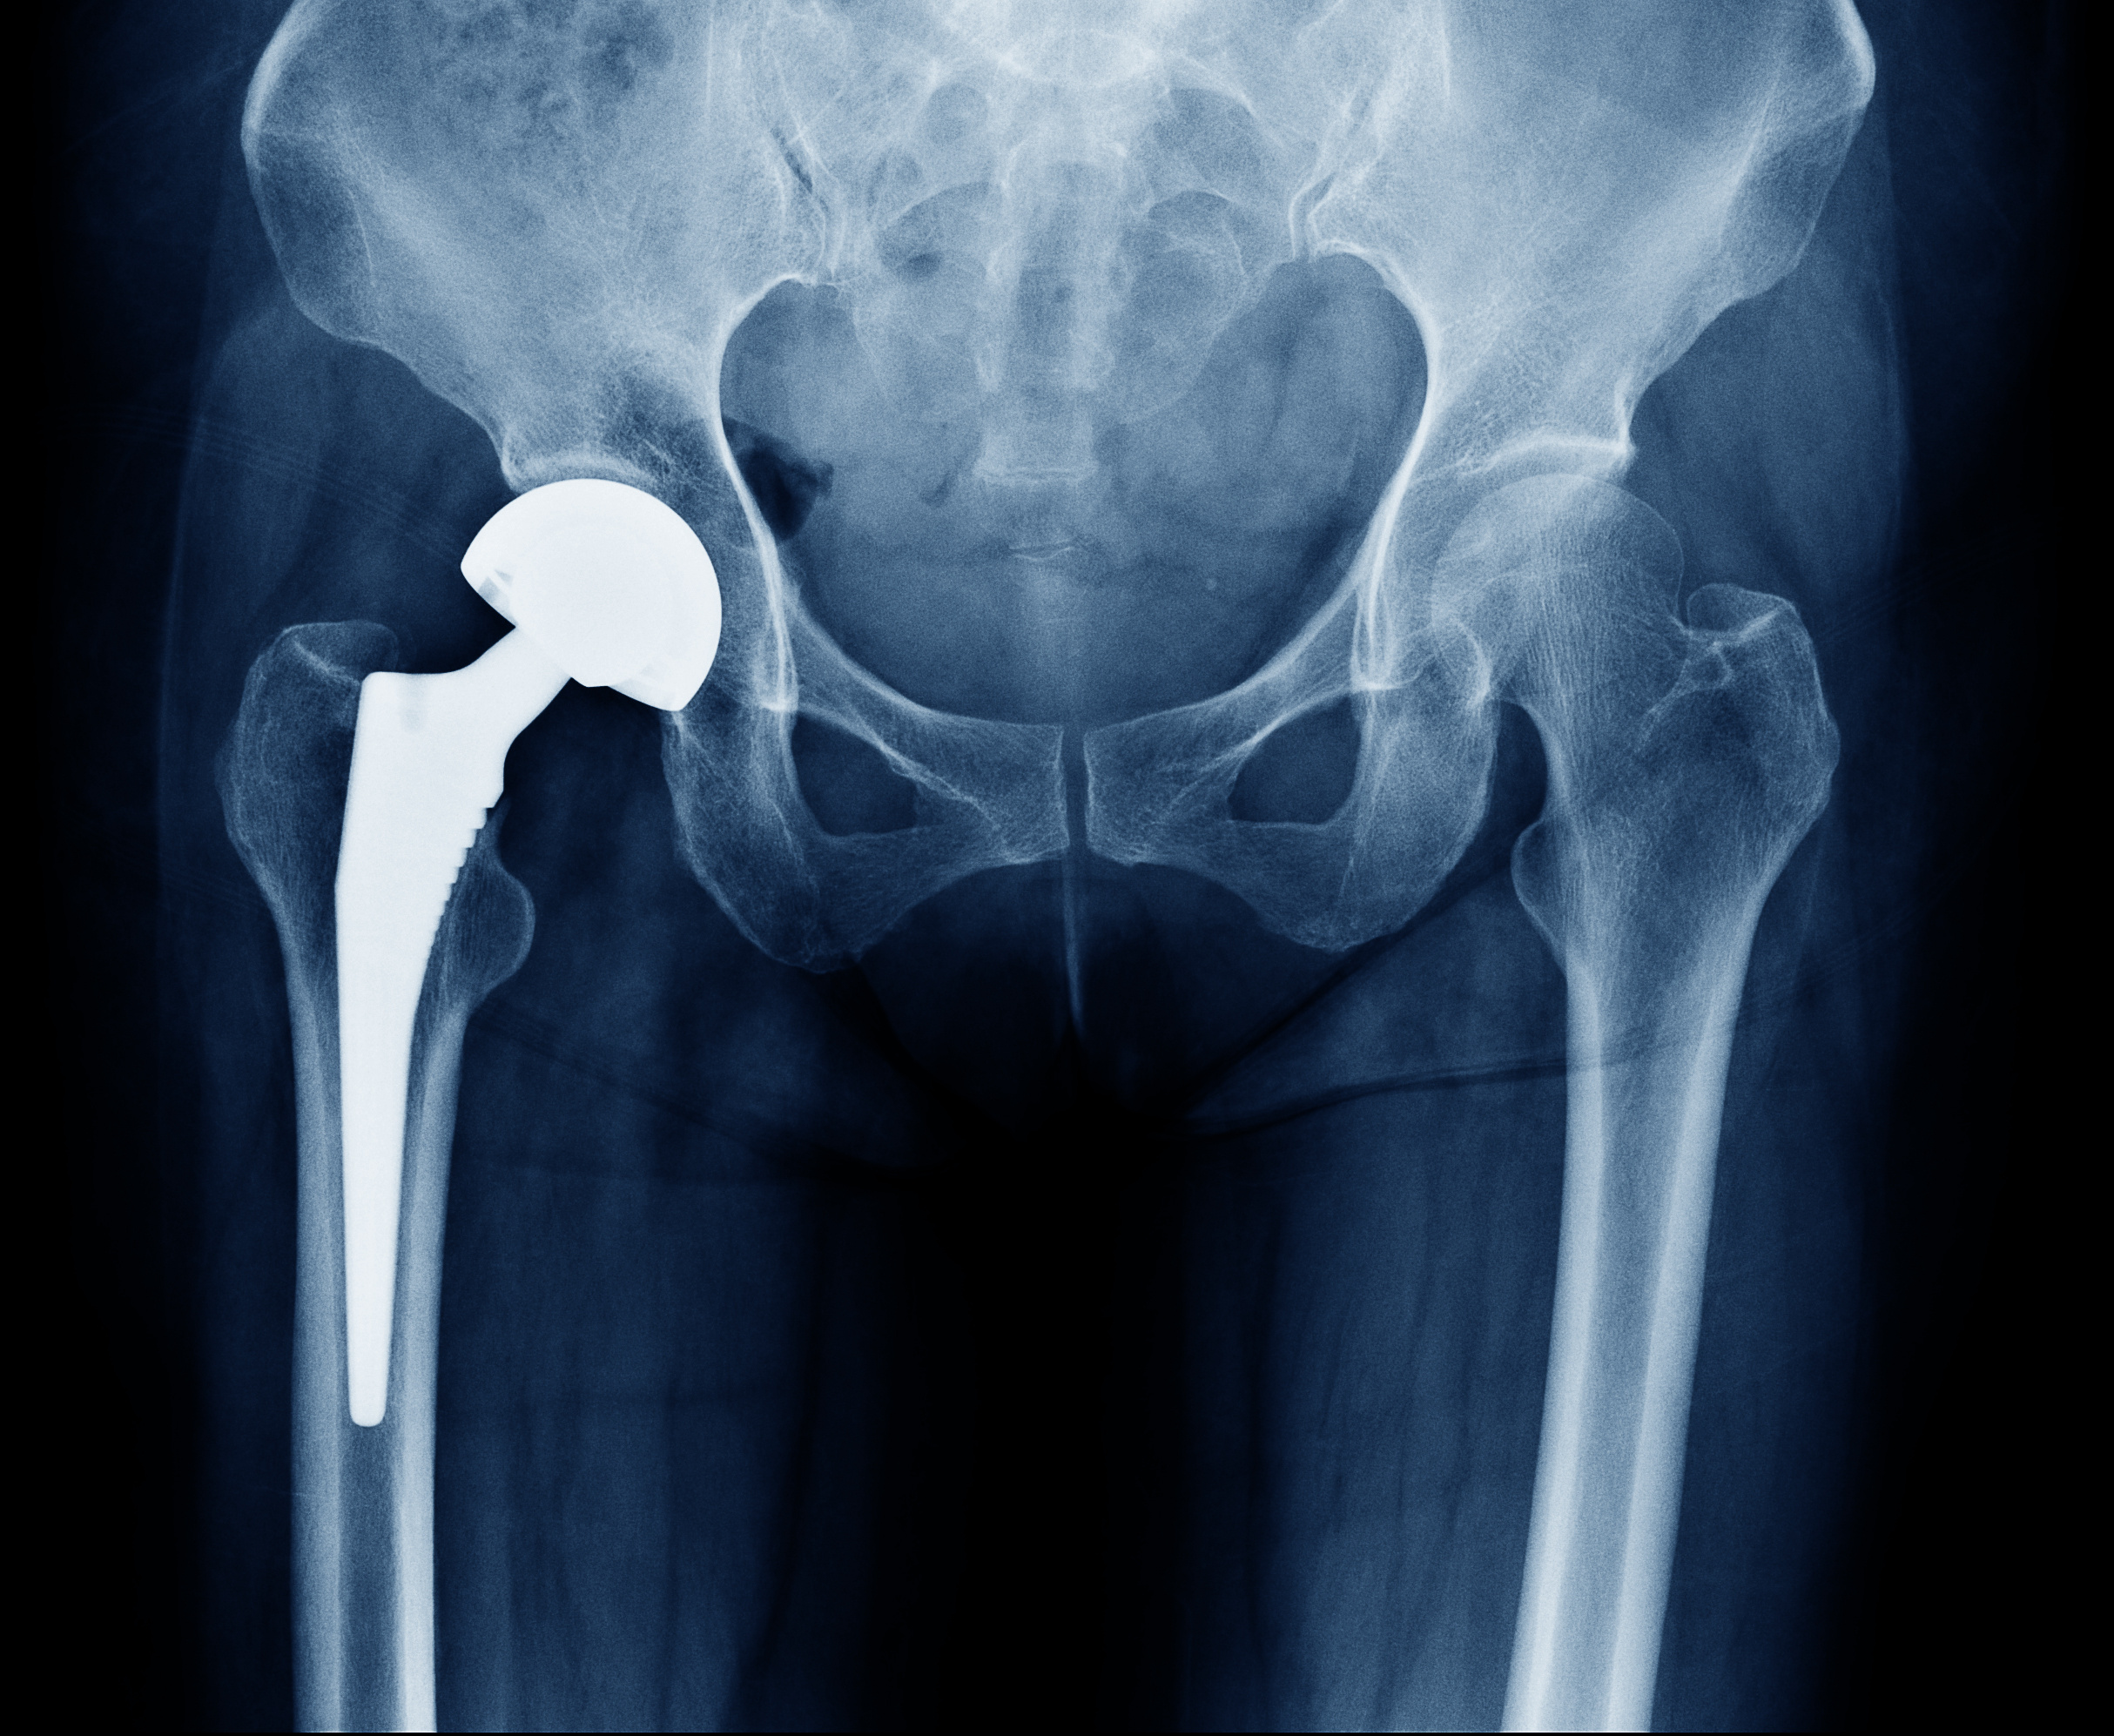

Hip replacement surgery is a procedure in which a damaged or worn-out hip joint is replaced with an artificial joint, called a prosthesis. It is a common and highly successful procedure that helps relieve pain and improve mobility in people suffering from severe hip conditions.